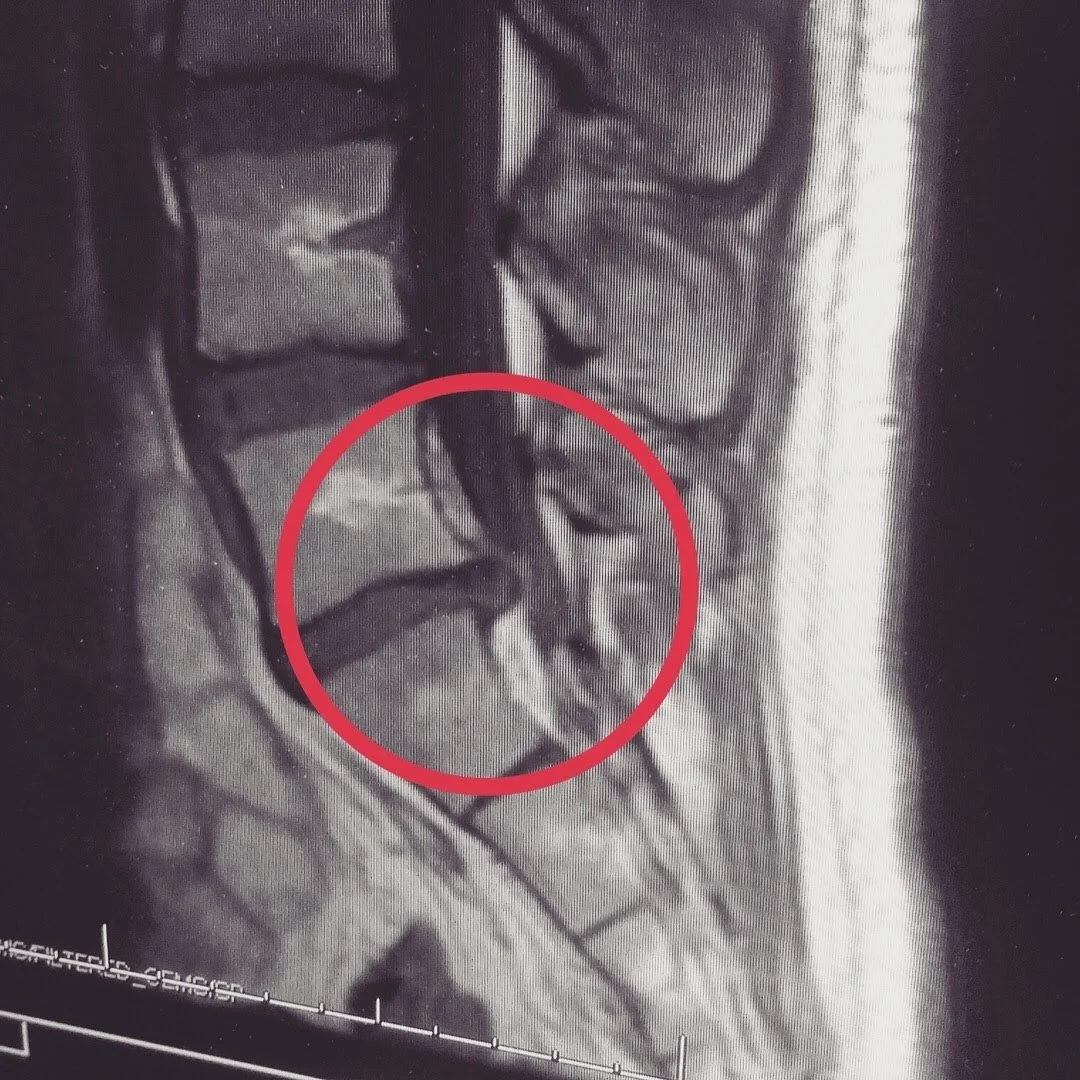

One day, I was working out and decided to push myself a bit harder than usual on the deadlift. I felt fine in the moment, but I woke up the next morning with a deep ache in my left hip. Over the course of the next month, that deep ache turned into a sharp pain that would shoot down the back of my left leg for the next four years. An MRI would later confirm that I had herniated two discs in my lower back. I was 18 years old.